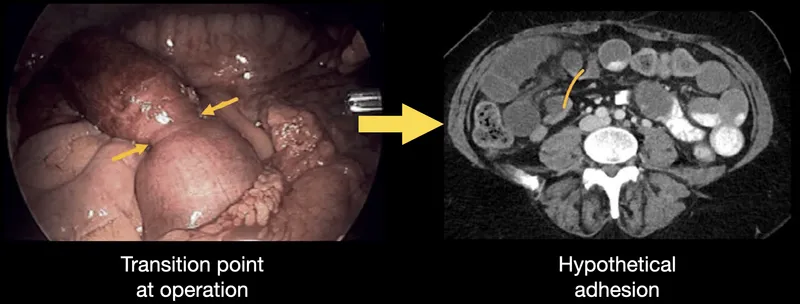

- Etiology: Adhesions (most common), hernias, tumors. 📌 "ABC": Adhesions, Bulges (hernias), Cancer.

⭐ Adhesions from previous surgery are the leading cause of small bowel obstruction in adults, while hernias are the second most common.

- Small Bowel Obstruction (SBO): Adhesions (post-op) are leading cause in adults; hernias second.